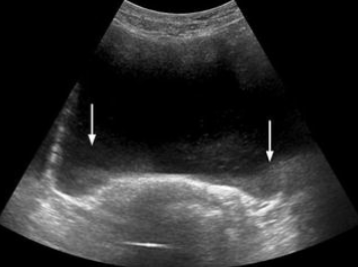

Shadowing

Caused by a highly attenuating structure

Reflection

Scattering

Absorption

Refraction

Combination of any of these

Complete absence of echo information behind attenuating structure

Can be reduced by spatial compounding

Different angles can angle behind these attenuating structures

highly, Reflection, Scattering, Absorption, Refraction, absence, spatial compounding, angles